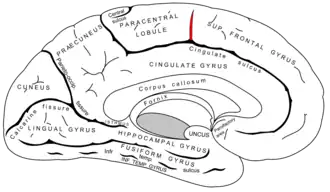

Medial view of a halved human brain (Paracentral lobule labeled at top center, in blue.) | |